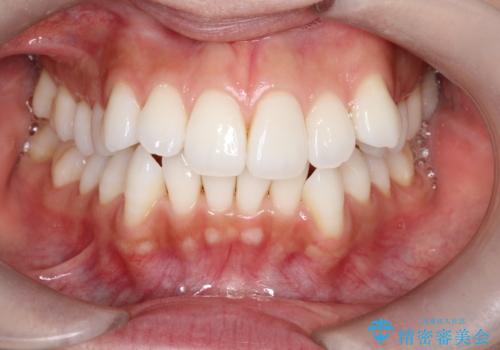

【抜歯インビザ】凸凹を綺麗になおしたい

- 前歯の凸凹を主訴に来院されました。

叢生量が多いため、抜歯が必要となるため、ワイヤー矯正をお勧めしましたが、患者さんの希望によりインビザラインで治療を開始しました。途中でワイヤーリカバリーを必要とせず終了でき患者さんには満足していただけました。

ワイヤー矯正よりも期間がかかっています。